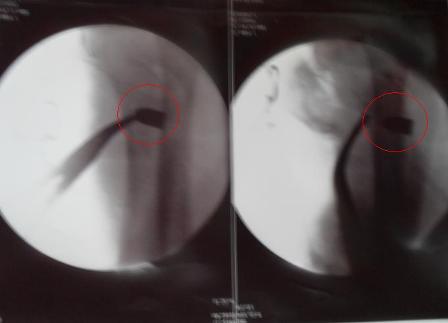

Hình ảnh viên đạn găm vào xương nạn nhân Hoàng Thị Trà Bác sĩ Thọ cho biết, hiện tại Hoàng Thị Trà đã qua cơn nguy kịch nhưng vẫn phải tiếp tục theo dõi. Cũng theo bác sĩ này, sau khi thực hiện ca mổ, cơ quan công an đã đến lập hồ sơ về vụ việc. Sau đó, đầu đạn cùng quần áo vấy máu của nạn nhân đã được bàn giao cho cơ quan điều tra.

Ngày 9.8 tại Phòng Hồi sức Khoa Ngoại tiết niệu - Bệnh viện Đa khoa TƯ Thái Nguyên, chị Hoàng Thị Trà (sinh viên trường ĐH Sư phạm) vẫn trong tình trạng lúc tỉnh lúc mê, khi tỉnh tỏ ra hoảng sợ, khóc và kêu đau. Bác sỹ Hoàng Thọ, Phó khoa Ngoại tiết niệu cho biết: “Chúng tôi phải tìm đầu đạn trong người bệnh nhân từ 21h00 đến 2h00 sáng. Đạn xượt qua phần mềm đùi trái, xuyên qua hố xương chậu và găm vào tủy xương đùi phải”. | ||||||||||||||